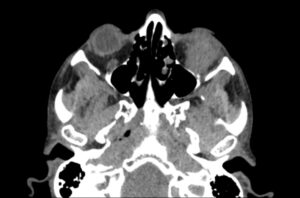

Inferior Rectus Abscess CT Axial Unannotated. JETem 2025